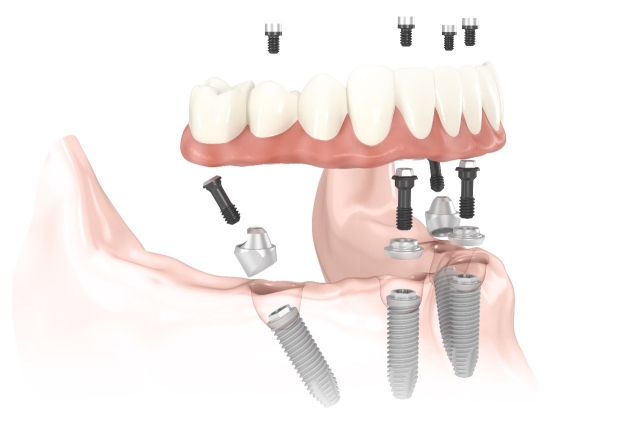

ALL-ON-4® Implants

The ALL-ON-4® technology is currently the most modern procedure in the field of implantology. The expression itself refers to all teeth being supported on four dental implants, per jawbone. This innovative technique provides a great solution for people with more missing teeth, even in case of complete toothlessness, to completely secure both upper and lower jaw area.

One of the biggest advantages of this technique is that the dentures are affixed to the implants at a special angle, which means that the implantation can be performed without sinus elevation or bone replacement surgery. Moreover, the extraction of remaining teeth, the implantation itself and the insertion of temporary bridge are all carried out in one session.

All of these factors contribute to reduced healing time, optimised overall cost, gaining confidence and comfort in a shorter amount of time.